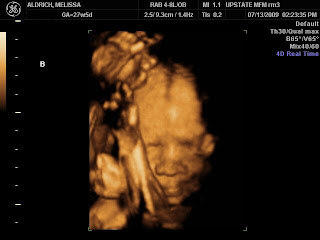

2009I can’t express how relieved I am to have visited the Maternal Fetal Specialist. Finally, I’ve had information poured into my type A brain and feel like I actually know what’s going on with the babies. WOOHOO! So here’s a bullet list of some of the more important information we received today.

- Baby A had rotated from footling breech to frank breech before the ultrasound. In the middle of the ultrasound she returned to footling breech. I love that stubborn little girl ๐

- If Baby A has club foot it’s relatively mild.

- The babies BOTH weigh approximately 2 lb 3 oz

- My cervix was declared a “triplet cervix”. It’s holding out at 4.8cm at 28.5 weeks

- Baby A is a little small in the torso despite weighing approximately the same as Baby B, so the Maternal Fetal Specialist will be seeing me for weekly ultrasounds to monitor blood flow from the placenta to Baby A. Every two weeks they’ll measure her growth.

- I’m still allowed to function normally because of the “triplet cervix”.

- The babies both really enjoy holding onto their feet above their heads.

- Baby A is my shy stubborn one.

- Baby B is my camera hogging diva. She even put her feet in front of Baby A’s head to block a decent head shot.

- Both girls are practice breathing already!

- Baby A has plenty of room to flip…if she chooses to do so.

- I didn’t even get close to passing out today from lying on the ultrasound table for over an hour. This one is quite comfy ๐

It was a good visit AND we got 3D ultrasound photos! I love how they are fascinated with their feet though it proved difficult to get face shots with all those feet. By the way, Baby B’s feet are the ones blocking Baby A’s shot. She did not want her sister to have the limelight!